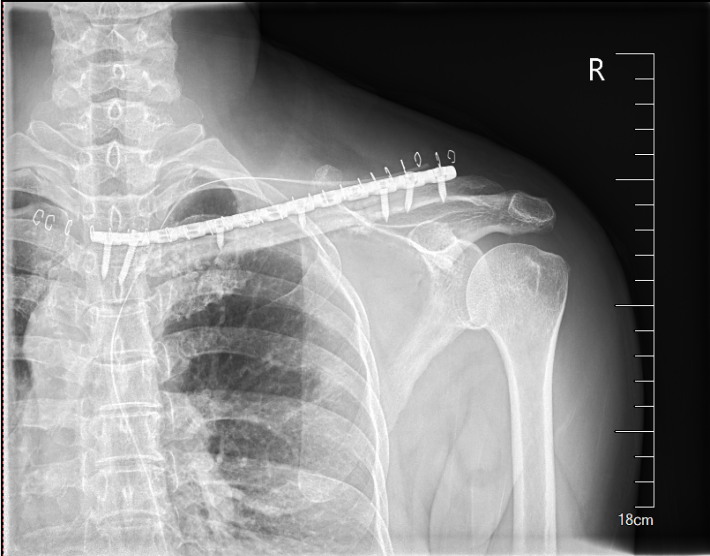

完善术前评估及准备后,王伟东副主任团队为患者实施了右锁骨胸骨端继发型软骨肉瘤扩大切除术+自体腓骨移植重建术。术中见肿物与颈总动脉、头臂静脉相邻紧密,王伟东副主任凭借扎实的手术技术,完整将肿瘤和临近大血管分离,完整切除肿瘤。目前患者伤口恢复良好,已逐步开始康复锻炼,肩关节活动无障碍。

图片 4.png

图片 5.png

图片 6.png